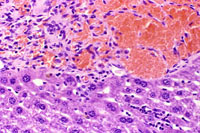

This hemangioma has isolated small clusters of hepatocytes; higher magnification shows proliferation of flattened endothelial cells.